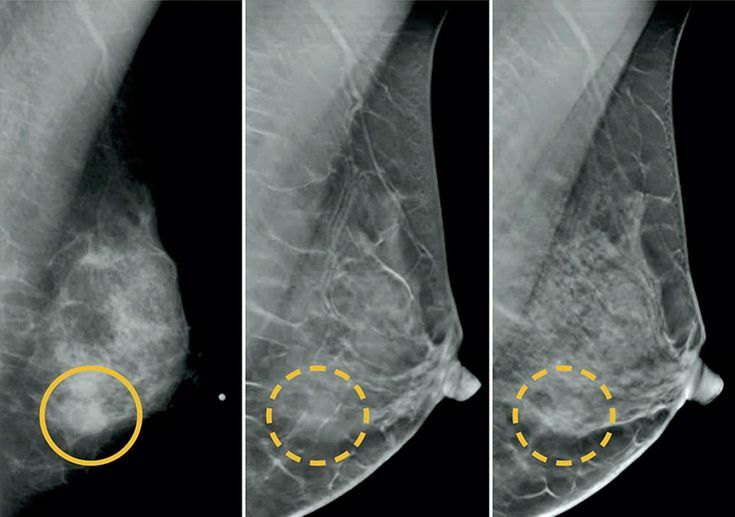

De acordo com o Instituto Nacional de Câncer (INCA), o câncer de mama é o tipo mais comum entre as mulheres no Brasil, com cerca de 74 mil novos casos estimados para 2025. A detecção precoce aumenta significativamente as chances de cura, chegando a até 95% de sucesso no tratamento quando diagnosticado em estágios iniciais.

A ampliação da faixa etária para realização da mamografia pelo SUS é, portanto, uma medida estratégica de saúde pública, que poderá impactar positivamente na redução da mortalidade feminina causada pela doença.